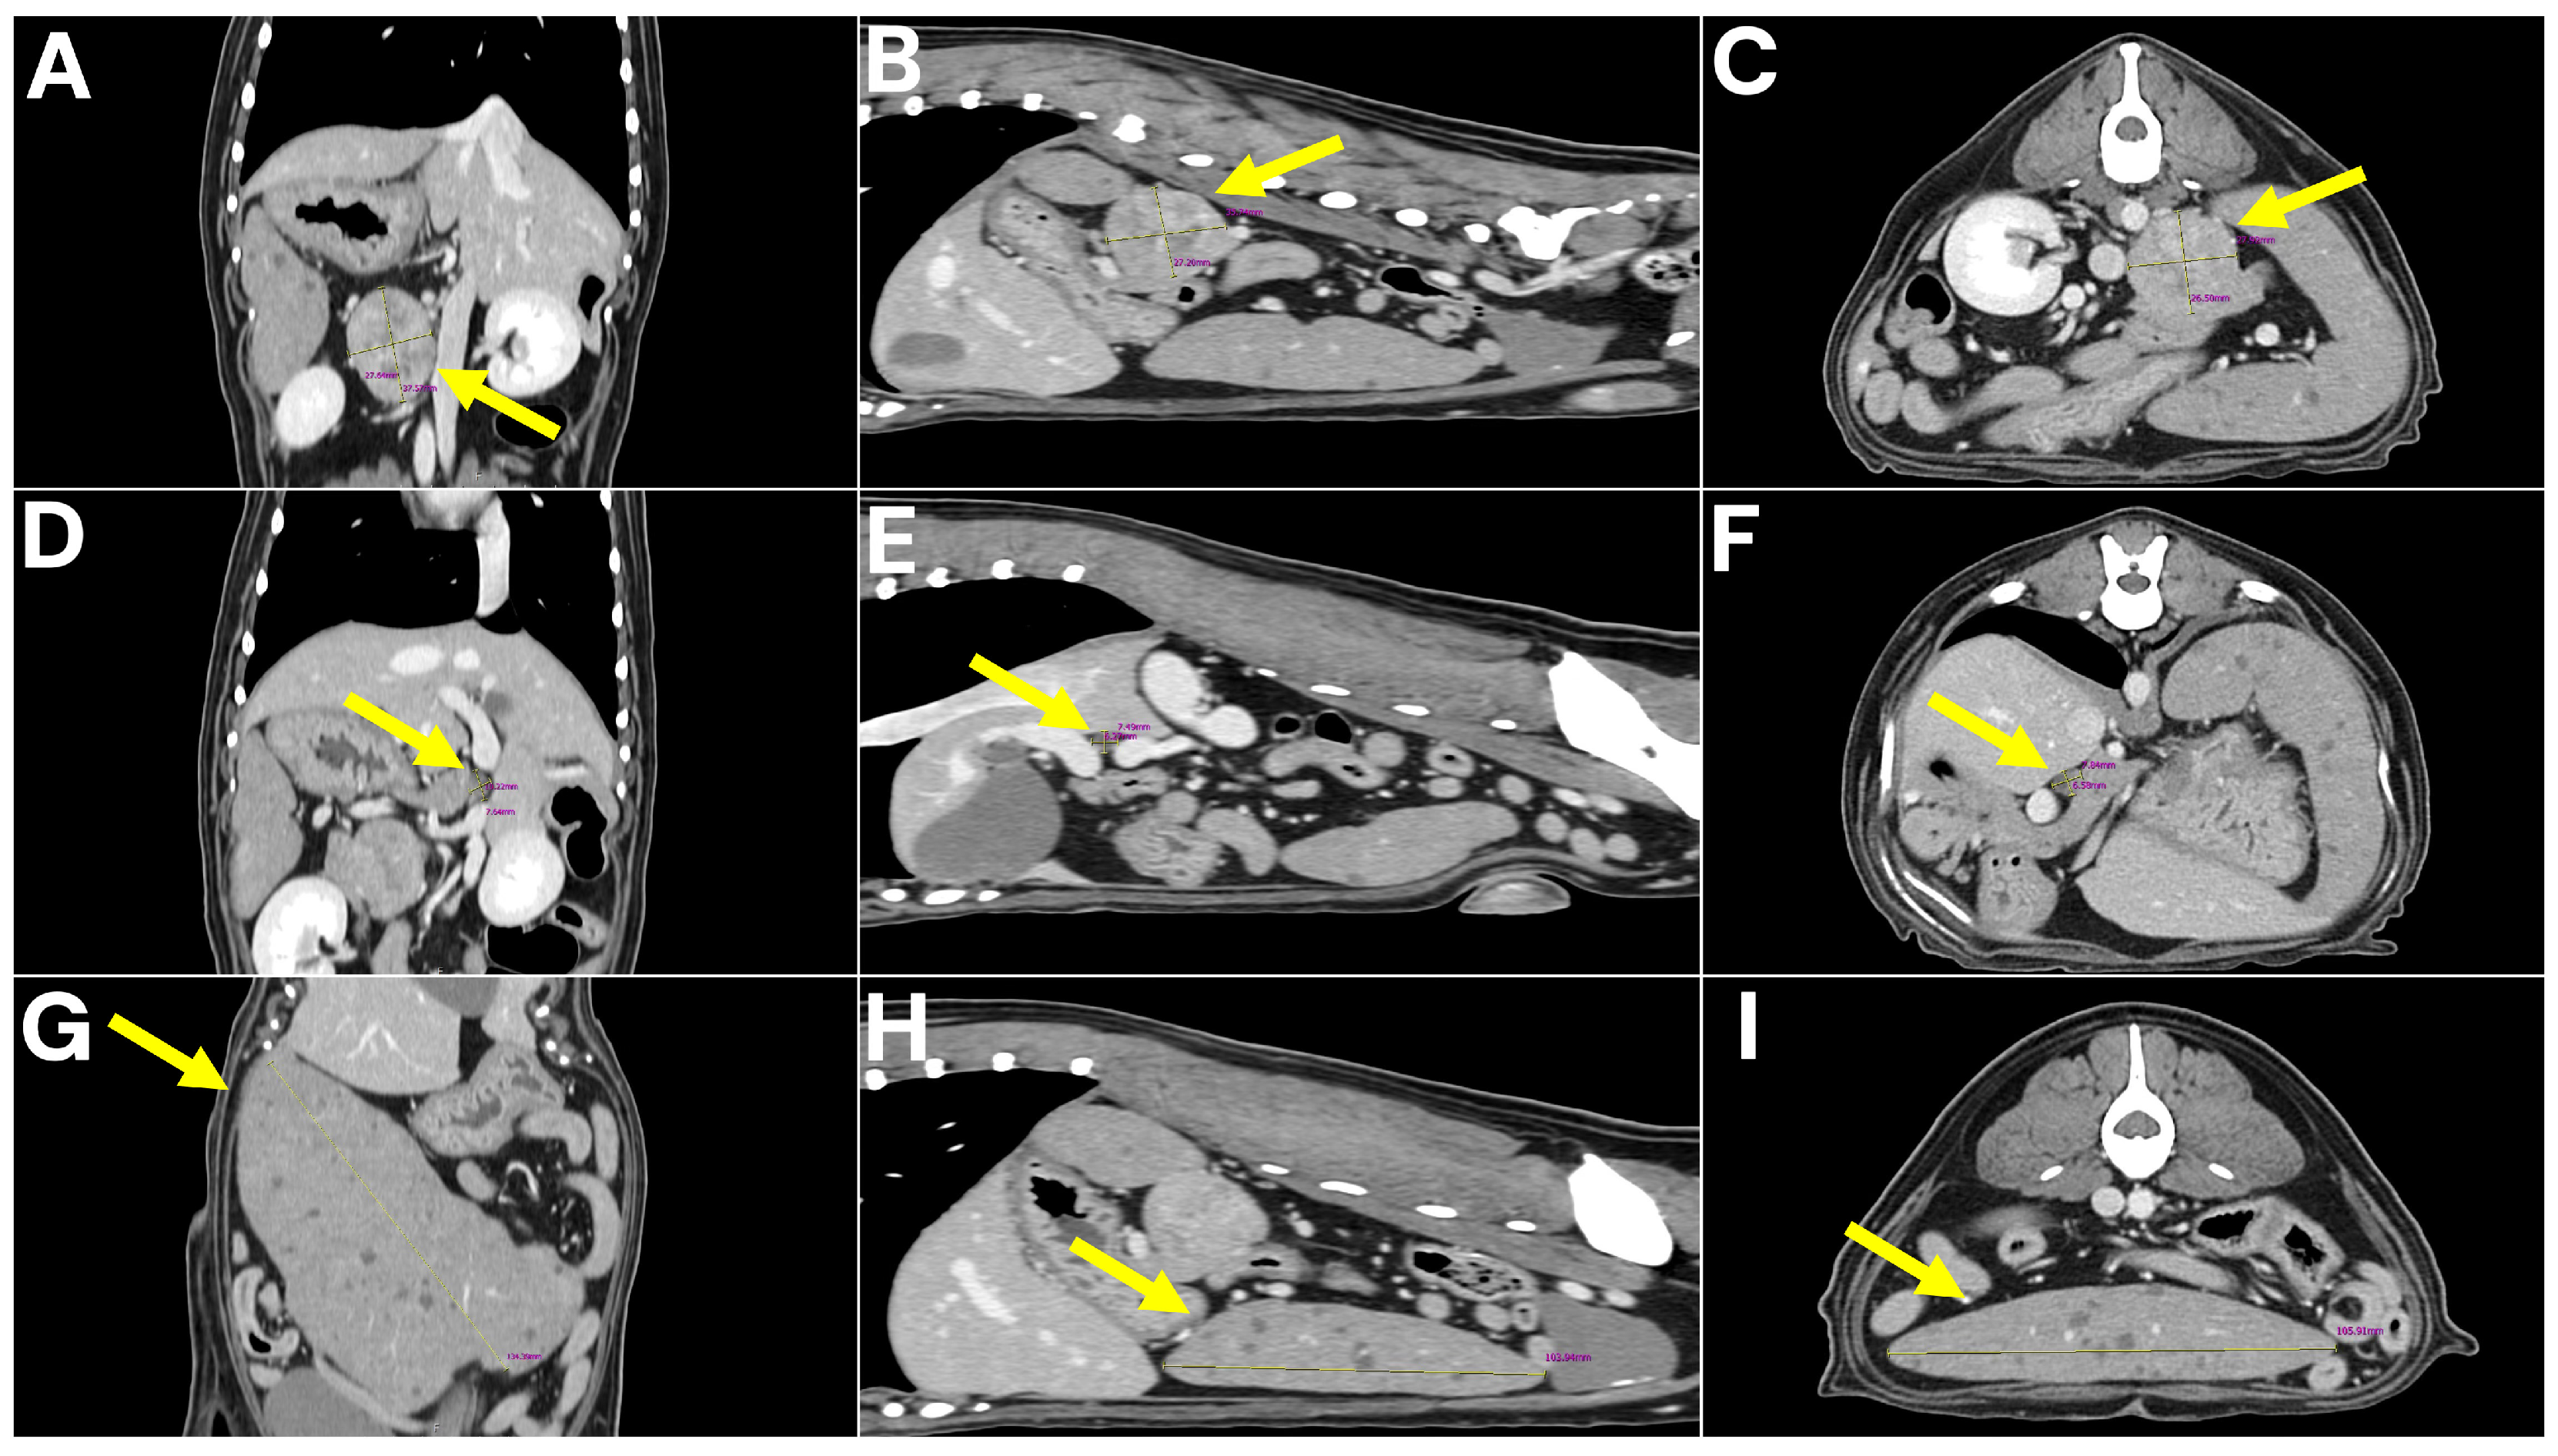

To further characterize the lesions and assess for metastatic disease, computed tomography (CT) was performed. No pulmonary metastasis was detected; however, multiple intra-abdominal masses with suspected metastatic lesions were observed. The retroperitoneal mass was delineated as a 4 × 3 × 3 cm lesion arising from the left adrenal gland, consistent with a tentative diagnosis of adrenal tumor. The spleen was enlarged and contained multiple nodular masses, while the mesenteric lymph nodes were markedly enlarged. In addition, a 7 mm lesion adherent to the wall of the hepatic portal vein (extraluminal mass) was detected and initially interpreted as a possible metastatic lesion (Figure 2).

Figure 2. CT images of abdominal tumors. (AC) Left adrenal gland mass (4 × 3 × 3 cm) shown in coronal, sagittal, and axial views, with arrows indicating the mass. (DF) Lesion adherent to the wall of the hepatic portal vein (7 mm) visualized in coronal, sagittal, and axial views, with arrows marking the site of vascular attachment. (GI) Splenic nodular masses demonstrated in coronal, sagittal, and axial views, with arrows identifying the nodular masses.